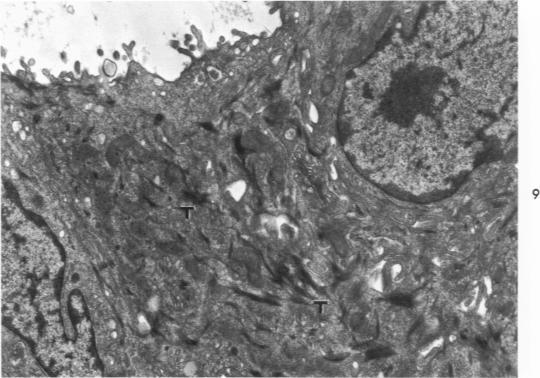

The major bronchi of swine, a dog and rabbits were examined with a scanning electron microscope and the fine structure of the openings of bronchial glands were studied three-dimensionally. The smallest areas of squamous metaplasia involved the duct openings. By examining serial sections with the light and transmission electron microscopes these early lesions were found localized at the opening of the bronchial gland duct. Cells intermediate to goblet and squamous cells were present in these lesions. Squamous metaplasia starting at this particular location is probably common and metaplasia can be an intracellular process.

用扫描电子显微镜检查了猪、狗和兔子的主支气管,并对支气管腺开口的精细结构进行了三维研究。鳞状化生面积最小的区域涉及导管开口。通过光学显微镜和透射电子显微镜检查连续切片,发现这些早期病变局限于支气管腺导管开口处。在这些病变中存在介于杯状细胞和鳞状细胞之间的细胞。从这个特定位置开始的鳞状化生可能很常见,并且化生可能是一个细胞内过程。